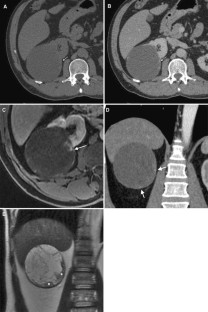

Fig. 3